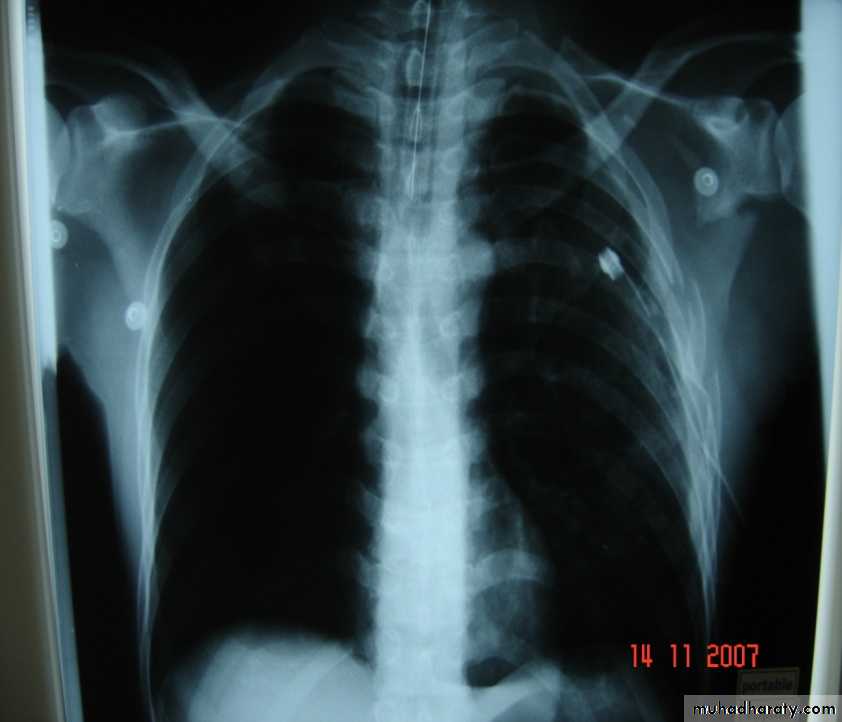

Widen mediasinum

• 6-Great vessels injuriesInjuries to the thoracic aorta and its branches can occur mainly with deceleration injury . Most patients with ruptured aorta die immediately but in 10% of patients the per aortic tissues and pleura are able to maintain the intravascular pressure producing false aneurysms ,which can be diagnose by CT angiography and needs immediate surgery .

Traumatic aortic disruption is a time-sensitive injury requiring rapid and accurate diagnosis to prevent death.